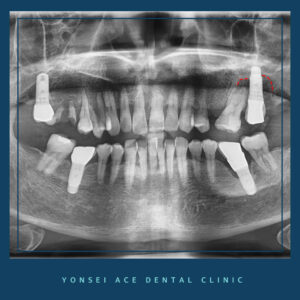

위의 사진 속 환자분도 마찬가지인데요.

환자분께서는 오른쪽 위 어금니가 파절되어

이를 해결하기 위해 본원을 찾아주셨지만,

왼쪽 위 어금니쪽에 식립한 임플란트 주변으로

염증이 나타난 것을 확인할 수 있었습니다.

파노라마 상으로 까맣게

보이는 것이 바로 염증인데요.

환자분께서는 평소 잇몸이 잘 붓고 쉽게

출혈이 났다고 하셨지만 크게

신경쓰지 않았다고 합니다.

환자분은 현재 염증이 심해 재식립이 필요하였고,

염증으로 인해 잇몸뼈가 녹아 치조골이식술도

함께 동반되어야 하는 상황이었습니다.

인접치아 또한 치아를 상실한 채 오랫동안

방치하여 빈공간으로 치아가 치우쳐 져있었으며,

전반적으로 치료가 시급한 상황이었는데요.